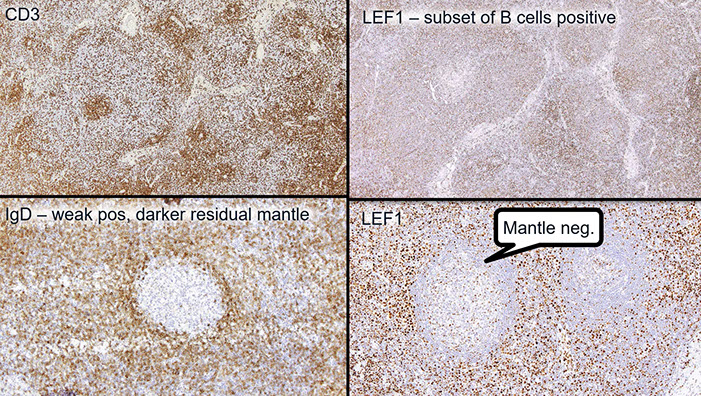

CLL IHC. CD3 positive (upper left), LEF1 staining a subset of B-cells (upper right), IgD weakly positive in the tumor cells and more strongly (darker) positive in the residual mantle zone (bottom left), with LEF1 negative in the mantle zone (bottom right)